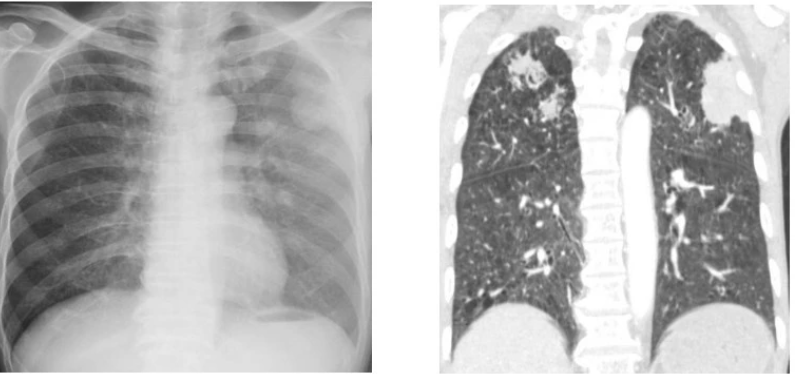

Tổn thương phổi hoại tử hai bên do nhiễm giun lươn. Ảnh: BVCC.

Tại khoa Hô hấp - Hồi sức tim mạch, kết quả chụp cắt lớp vi tính ngực và ổ bụng cho thấy hẹp môn vị nghi do ký sinh trùng và tổn thương phổi hoại tử hai bên. Xét nghiệm dịch rửa phế quản phát hiện ký sinh trùng, bệnh nhân được chẩn đoán nhiễm giun lươn nặng ở phổi và điều trị đặc hiệu theo phác đồ.